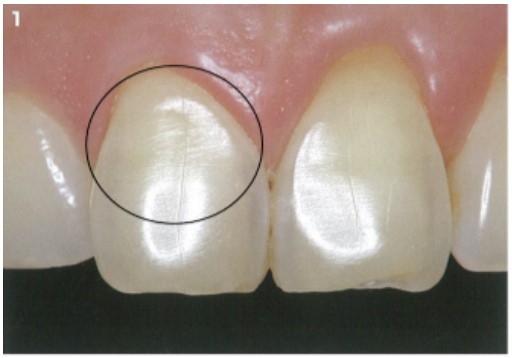

ラミネートベニア

歯の色調の改善や、軽い歯並びの改善(歯のすき間を隠すことも出来ます)のために歯の表面に薄いセラミックを特殊な接着剤で張り付ける治療法です。歯の表面を削る量はほんのわずかです。(状態によっては歯を削らない場合があります)

また治療にかかる期間も数回のご来院で終わります。ご自分の歯の色調が基本となるので、色調の大幅な改善を希望される場合は、ベニア治療の前にホワイトニング治療をお勧めすることもございます。

治療後